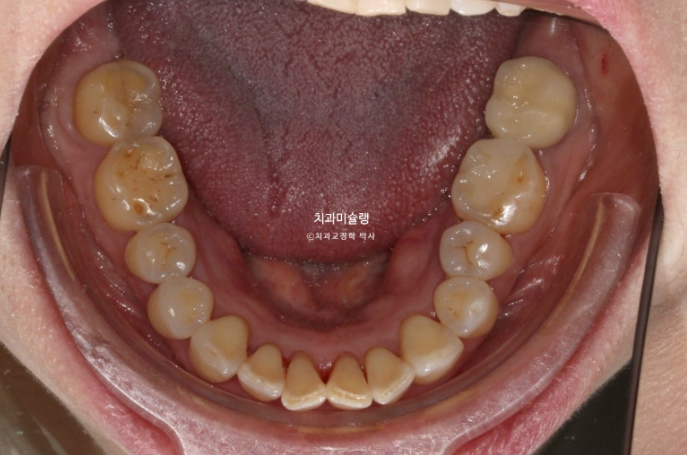

레진이 차지하는 비중이 컸습니다

아래 앞니 사이사이는 공간이 없는 데 위 앞니 사이사이에만 큰 공간이 있다면

이 공간을 교정으로 100% 메꿀 수 없습니다.

최대한 공간을 줄여놓고 남은 미세공간은 레진으로 마무리 해야 합니다.

인비절라인 라이트 치료 권유드렸습니다.

아래 앞니는 원래 있던 블랙트라이앵글을 없앨 겸 치간삭제를 동반하기로 합니다.

또한 아래 앞니가 위 앞니를 밀어내어 위 앞니 벌어짐이 심해지지 않도록 아래 앞니는 함입도 필요합니다.